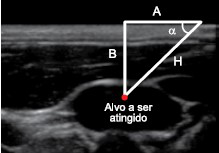

Na prática diária da medicina, a trigonometria pode ser utilizada para determinar, por exemplo, a inclinação que devemos dar a uma agulha com o objetivo de atingir o local desejado. A imagem indica a anatomia ultrassônica da veia jugular interna de um paciente. Nessa imagem, H representa a medida do trajeto retilíneo da agulha que incidirá na pele do paciente, A representa a distância, medida na pele retilínea do paciente, entre o ponto de incisão da agulha e o ponto correspondente à projeção ortogonal do alvo a ser atingido sobre a pele, e B representa uma medida que depende da anatomia de cada paciente.

(https://ccforum.biomedcentral.com. Adaptado.)

Seja (A, !$ α !$) um par ordenado, com A em centímetros e !$ α !$ em radianos. Suponha que a imagem de ultrassom apresentada indique ao médico B = 2 cm e cinco pares (A, !$ α !$), dados por

S1 = !$ \begin{pmatrix}2 \sqrt{3},\dfrac{π}{3} \end{pmatrix} !$, S2 = !$ \begin{pmatrix}3\sqrt{3},\dfrac{π}{6} \end{pmatrix} !$, S3 = !$ \begin{pmatrix}2, \dfrac{π}{4} \end{pmatrix} !$, S4 = !$ \begin{pmatrix}\dfrac{2 \sqrt{3}}{3},\dfrac{π}{6} \end{pmatrix} !$ e S5 = !$ \begin{pmatrix}1,\dfrac{π}{4} \end{pmatrix} !$ será atingido corretamente.

Nessas condições, dentre os cinco pares (A, !$ α !$), aquele que atingirá corretamente o alvo será